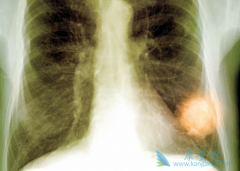

泰瑞莎 (AZD9291)在国内获批有一段时间了,这个肺癌靶向药一直以来备受患者的关注,不论是一线还是三线,均能使患者获得好的收益。而PD-1药物也是近两年比较火的抗癌药物,在肺癌治疗上有显着的疗效,那泰瑞莎和PD-1药物能否强强联手呢?它的效果是增 ...

FDA授予 克唑替尼 (Crizotinib)突破性药物资格,是基于一项全球I期研究(Study 1001)扩展队列的分析数据。该队列共纳入50例证实为ROS1重排的晚期非小细胞肺癌(NSCLC)患者,研究中对患者采用标准方案的口服剂量克唑替尼 (250mg,2次/天)治疗,评估药物的 ...